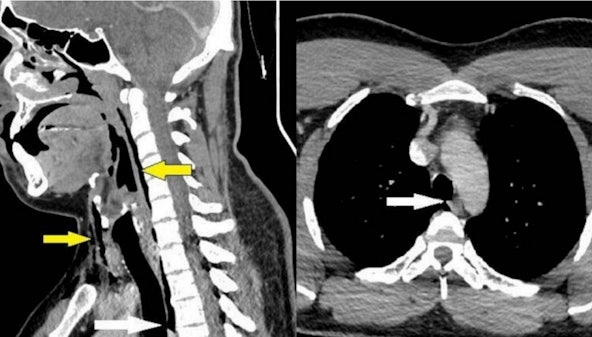

Cô gái 21 tuổi bất ngờ phát hiện ung thư nhờ 1 thứ trên cổ rất ít người để ý, thường đổ lỗi cho tăng cân

Đôi khi, một vài thay đổi nhỏ trên cơ thể, không gây đau đớn hay khó...